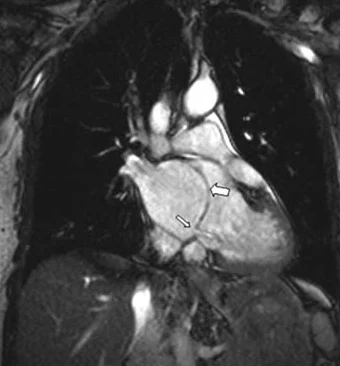

La resonancia cardíaca ofrece una visión más completa de la estructura y función del corazón. Se utiliza para diagnosticar una amplia variedad de patologías cardíacas, tales como obstrucción de las arterias, cardiomiopatías y anomalías estructurales, permitiendo un tratamiento más preciso.

La resonancia magnética cardíaca es un examen de imagen que permite evaluar la estructura y función del corazón. Diagnostica problemas cardiacos como obstrucciones y cardiomiopatías.